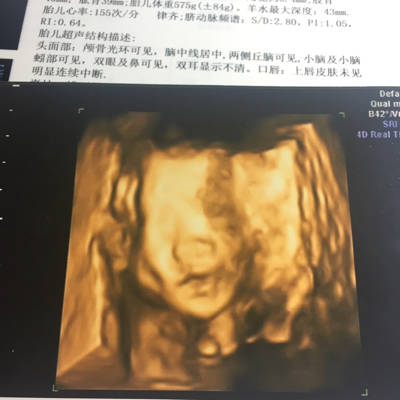

前两天做的四维,四维图上看起来正常,可是放大的照片看起来像兔唇,问

今天照了三围,但看图片,宝宝好像有点是兔唇,但b超单上又写"上唇皮肤

请各位宝妈帮我看一下这个四维是兔唇吗?

四维照片宝宝这样算兔唇吗